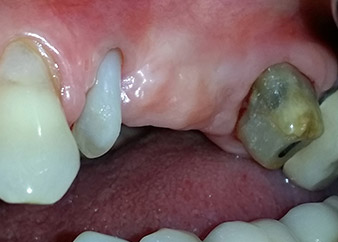

Mujer de 58 años de edad, que además es una apreciada colega y amiga, y se quejaba de dolor y de un aumento en la movilidad del pilar del puente de la pieza dental 24. También había inflamación periodontal, con bolsas de una profundidad de 7 mm en sentido mesiobucal y más de 12 mm en sentido distal, así como furcación de tercer grado. Asimismo, la radiografía reveló una lesión periodontal extensa alrededor de la región apical de la pieza dental 24 (figura 1) tratada previamente con endodoncia (alio loco).

Un mes después, en el día de la intervención, el dolor y la inflamación se habían reducido al mínimo en la pieza 24, pero seguía habiendo una movilidad de clase II de Miller. Después de la apertura de los colgajos y de la limpieza del tejido infectado periapical y perirradicular, la extensión del defecto óseo quedó evidente (figuras 2 y 3).

la raíz bucal de la pieza 24 mostraba una pérdida total del hueso y de la fijación

Fig. 2 y 3: Después de abrir los colgajos, un mes después de realizar la revisión endodóntica y de iniciar la terapia periodontal en toda la boca, la raíz bucal de la pieza 24 mostraba una pérdida total del hueso y de la fijación.